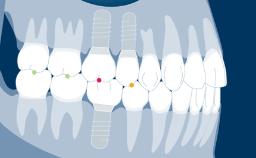

Introduction to Implant Dentistry

Implant Designs and Characteristics

Learning Module